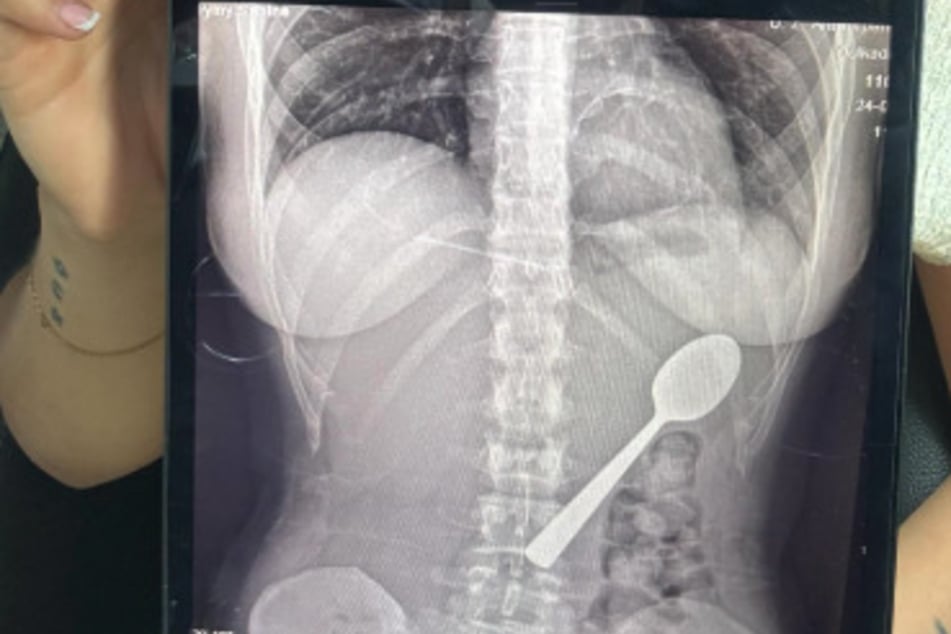

Als ihr Freund am Abend nach Hause kam, behielt sie den Vorfall vorerst für sich. Viel zu sehr schämte sie sich für das, was passiert war. Doch nach dem Abendessen bemerkte sie dann, wie sie sich immer schlechter fühlte. Und das war auch kein Wunder - schließlich steckte ein 17 Zentimeter langer Löffel in ihrem Bauch.

Kurzerhand fuhr sie also ins Krankenhaus, wo ihr die Ärzte mitteilten, dass der Löffel zu groß sei, um ihren Körper auf natürlichen Wege wieder zu verlassen. Also musste er von einem Mediziner entfernt werden.

"Sie mussten [den Löffel] in meinem Magen drehen, was zu einer kleinen Magenblutung führte. Das war nicht angenehm, aber als er herauskam, war ich einfach nur erleichtert."